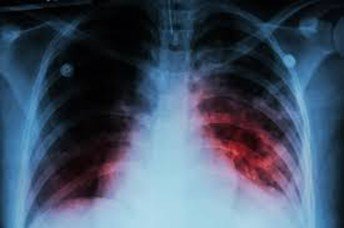

Tuberculosis & HIV Care

We offer confidential, compassionate care for TB and HIV patients with regular monitoring, medication adherence support, and counseling—ensuring better outcomes and reduced transmission risks.